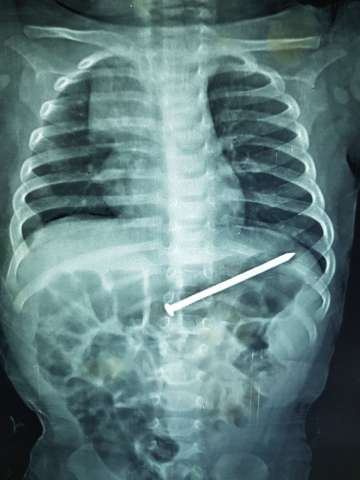

فريق جراحى يستخرج مسمار 6 سم بالمنظار من طفل 9 شهور

صرح الدكتور أحمد الرفاعى مدير مستشفى الأطفال بجامعة المنصورة عن تمكن فريق جراحى بوحدة الجهاز الهضمى بمستشفى الأطفال بجامعة المنصورة من اجراءعملية استخراج مسمار طوله 6 سم باستخدام المنظار بدون اى جرح أو مضاعفات أو تدخل جرحى من بطن طفل عمره ٩شهور.

وأشار الدكتور محمد عز الرجال أن الطفل كان يلعب مع اخوه ٣سنوات فى عدم وجود الام بعدها جاء الطفل الكبير يخبر الأم أن الطفل الصغير بلع مسمار.

وقامت الام خلال سته ايام بمحاولة استخراج المسمار طبيا حتى جاءت مستشفى الاطفال الساعه التاسعة صباحا وتم عرض الحالة على الفريق الطبى وتم اجراء الاشعه لتحديد مكان المسمار وقرر الفريق استخراجه باستخدام المنظار والحمد لله تمت العمليه بسلام من غير مضاعفات والطفل غادر المستشفى فى نفس اليوم.